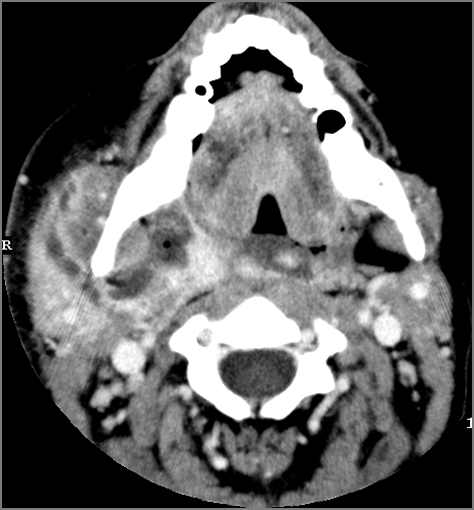

There is abscess within the parotid gland. [Yes/No]

There is edema or abscess within the fat surrounding the parotid gland or of the adjacent masticator space or other spaces. [Yes/No]

There are enlarged abnormal intraparotid, facial or posterior neck lymph nodes. [Yes/No]